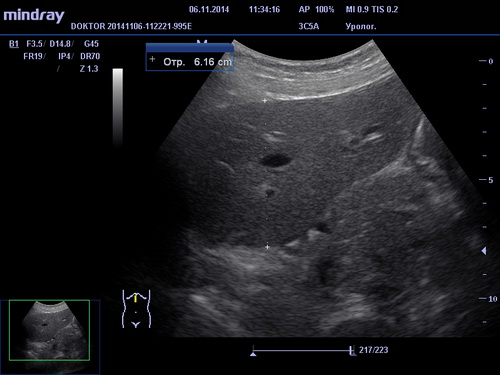

УЗИ брюшной полости

При помощи УЗИ брюшной полости возможна диагностика различных заболеваний и отклонений в состоянии печени, желчного пузыря, поджелудочной железы и селезенки, таких как холецистит, панкреатит, жировой гепатоз, хронический гепатит, цирроз печени, наличие опухолей и других образований. В зависимости от обследуемого органа и выявленной патологии пациенту назначается соответствующее лечение терапевтом, гепатологом или хирургом.